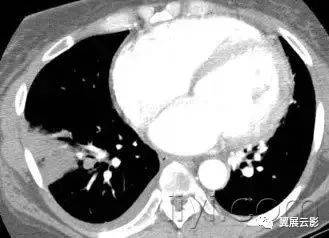

四、空气滞留(air trapping)

病理:阻塞远端的气体滞留(通常是部分性)

CT:在呼气末CT上表现为实质密度升高程度低于正常肺实质,体积减小程度降低。当空气滞留较轻或者弥漫的时候,比较呼气末和吸气末CT是有帮助的。阻塞性血管病变造成的低灌注也表现低密度,有时候与本病鉴别比较困难。但是可以发现相关的气道病变,与血管性病变不同。